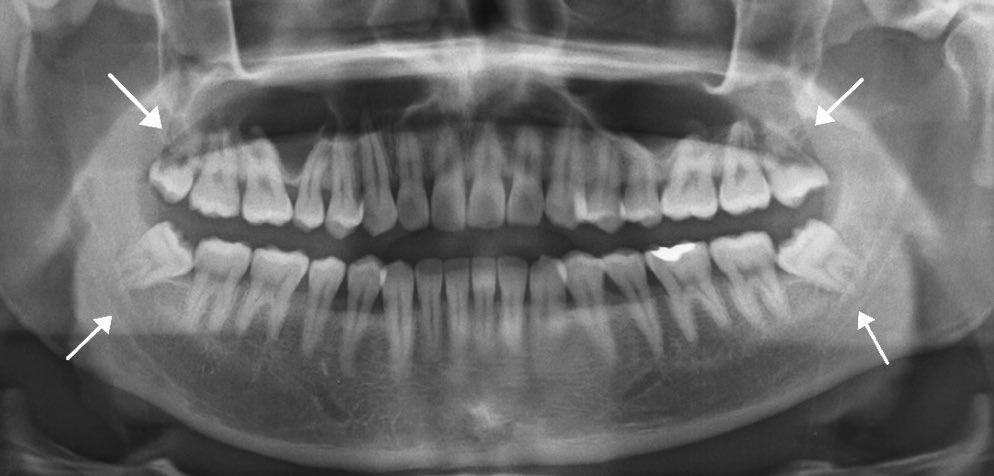

أضراس العقل أو الرحى الثالثه: هي أخر أضراس موجوده في الفك من جهة الخلف وكل أنسان يكون عنده ٤ في كل ربع واحد ، يكتمل بزوغه في اواخر *الطعشات* 😆 وبداية العشرينات ، هاذي صورة أشعة توضح مكانه حطيت لكم سهم عليهم 👇🏼